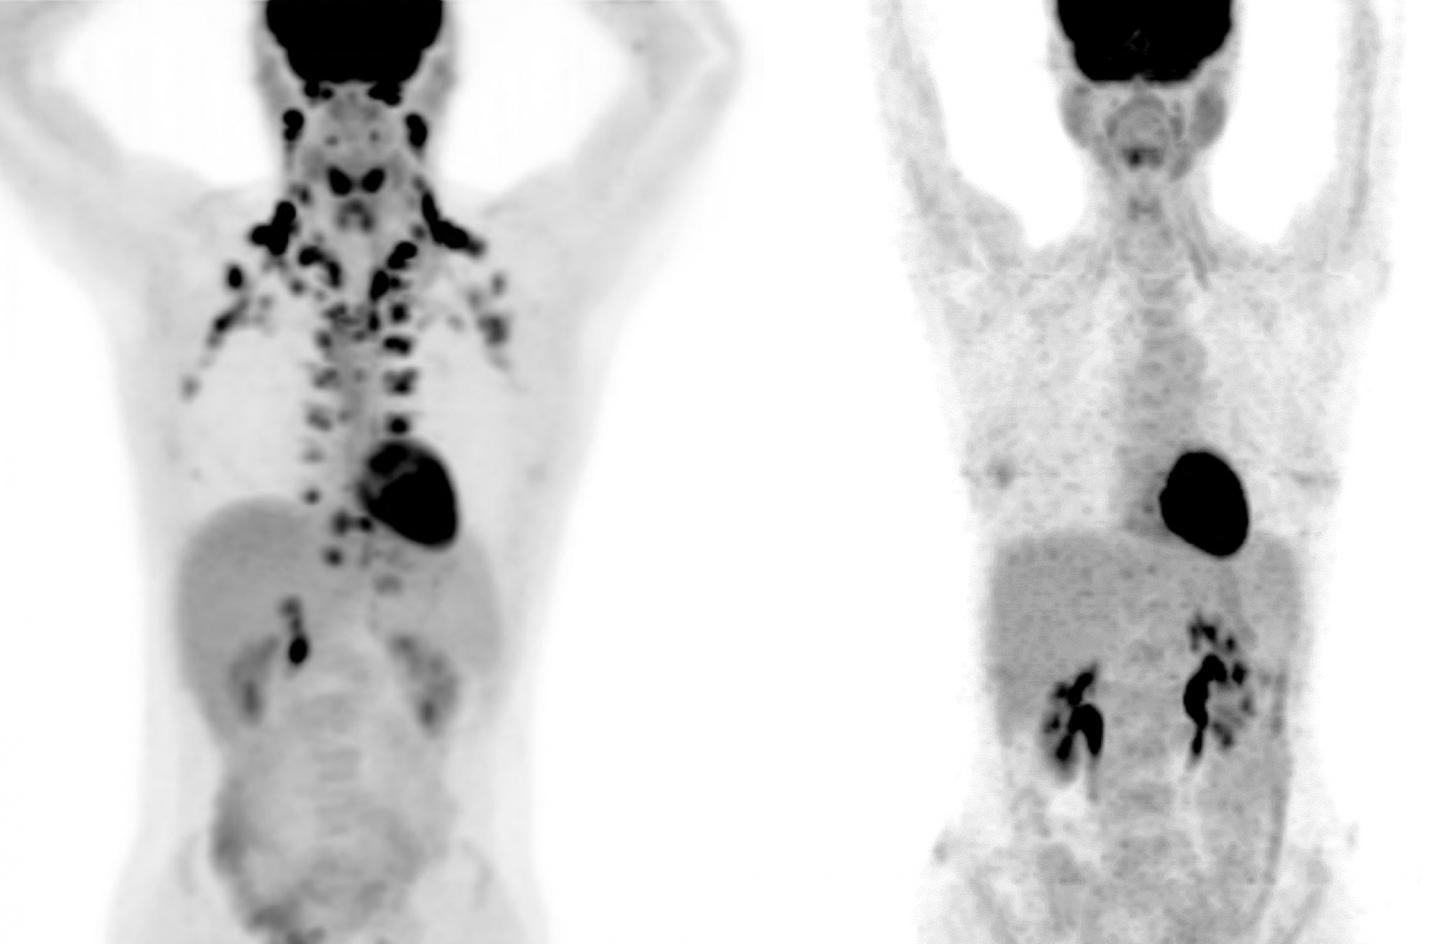

Analysis of PET scans from more than 50,000 subjects found detectable brown fat levels correlated with better metabolic and cardiac health

In these PET scans, the person on the left has abundant brown fat around the neck and cervical spine, while the person on the right has no detectable brown fat

Courtesy of MSKCC radiologists Andreas G. Wibmer and Heiko Schöder